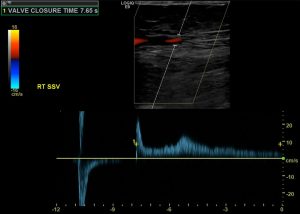

In addition, ultrasound can examine the flow within veins. Ultrasound is the most common test to diagnose venous insufficiency. It is used to map areas where the valves are not functioning properly. Why would that be relevant to purple feet? Because some people have swollen purple feet. In such people, venous insufficiency is sometimes the cause.

The advantages of ultrasound are clear images, low cost, and low risk. But you have to know the limitation of the test. Unfortunately, ultrasound cannot suggest how much a finding is important. For example, it might show a narrowing in an artery. But perhaps the patient has enough redundant flow around that narrowing that makes it less important. For this reason, ultrasound should only be used if it is important to know where specific issues are. In fact, if you want to know if there is a problem at all, it is better to start with the ankle brachial index, and pulse volume recordings, as I noted above.